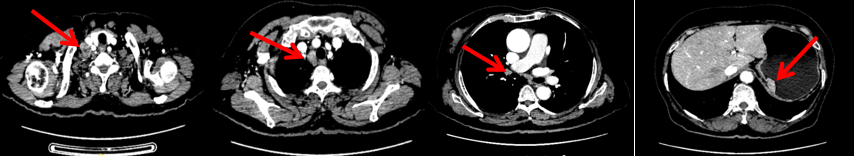

2023.6.26复查PET-CT

1.右乳外上象限乳腺癌病灶(22*16mm),对比2023-04-14 CT(26*24mm)较前缩小,FDG代谢活跃。右侧腋窝小淋巴结(5mm),较前稍缩小,代谢不活跃。右侧锁骨上区、上纵隔淋巴结转移瘤(24*18mm),现大小同前相仿,代谢活跃(SUV:6.7)。

2.现胃贲门部术后改变,术区未见明显异常活性灶。

3.左乳、左侧胶窝术后改变,未见明显异常活性灶。双肺小结节。考虑炎性结节可能,建议复查;双肺门及纵隔另反应性淋巴结。

2024-11-5复查CT:右乳外上象限占位(11mm×9mm),较前明显缩小;上纵隔及右肺门多发淋巴结转移缩小;右锁骨上区淋巴结较前增大。余部位未见肿瘤转移及复发征象。